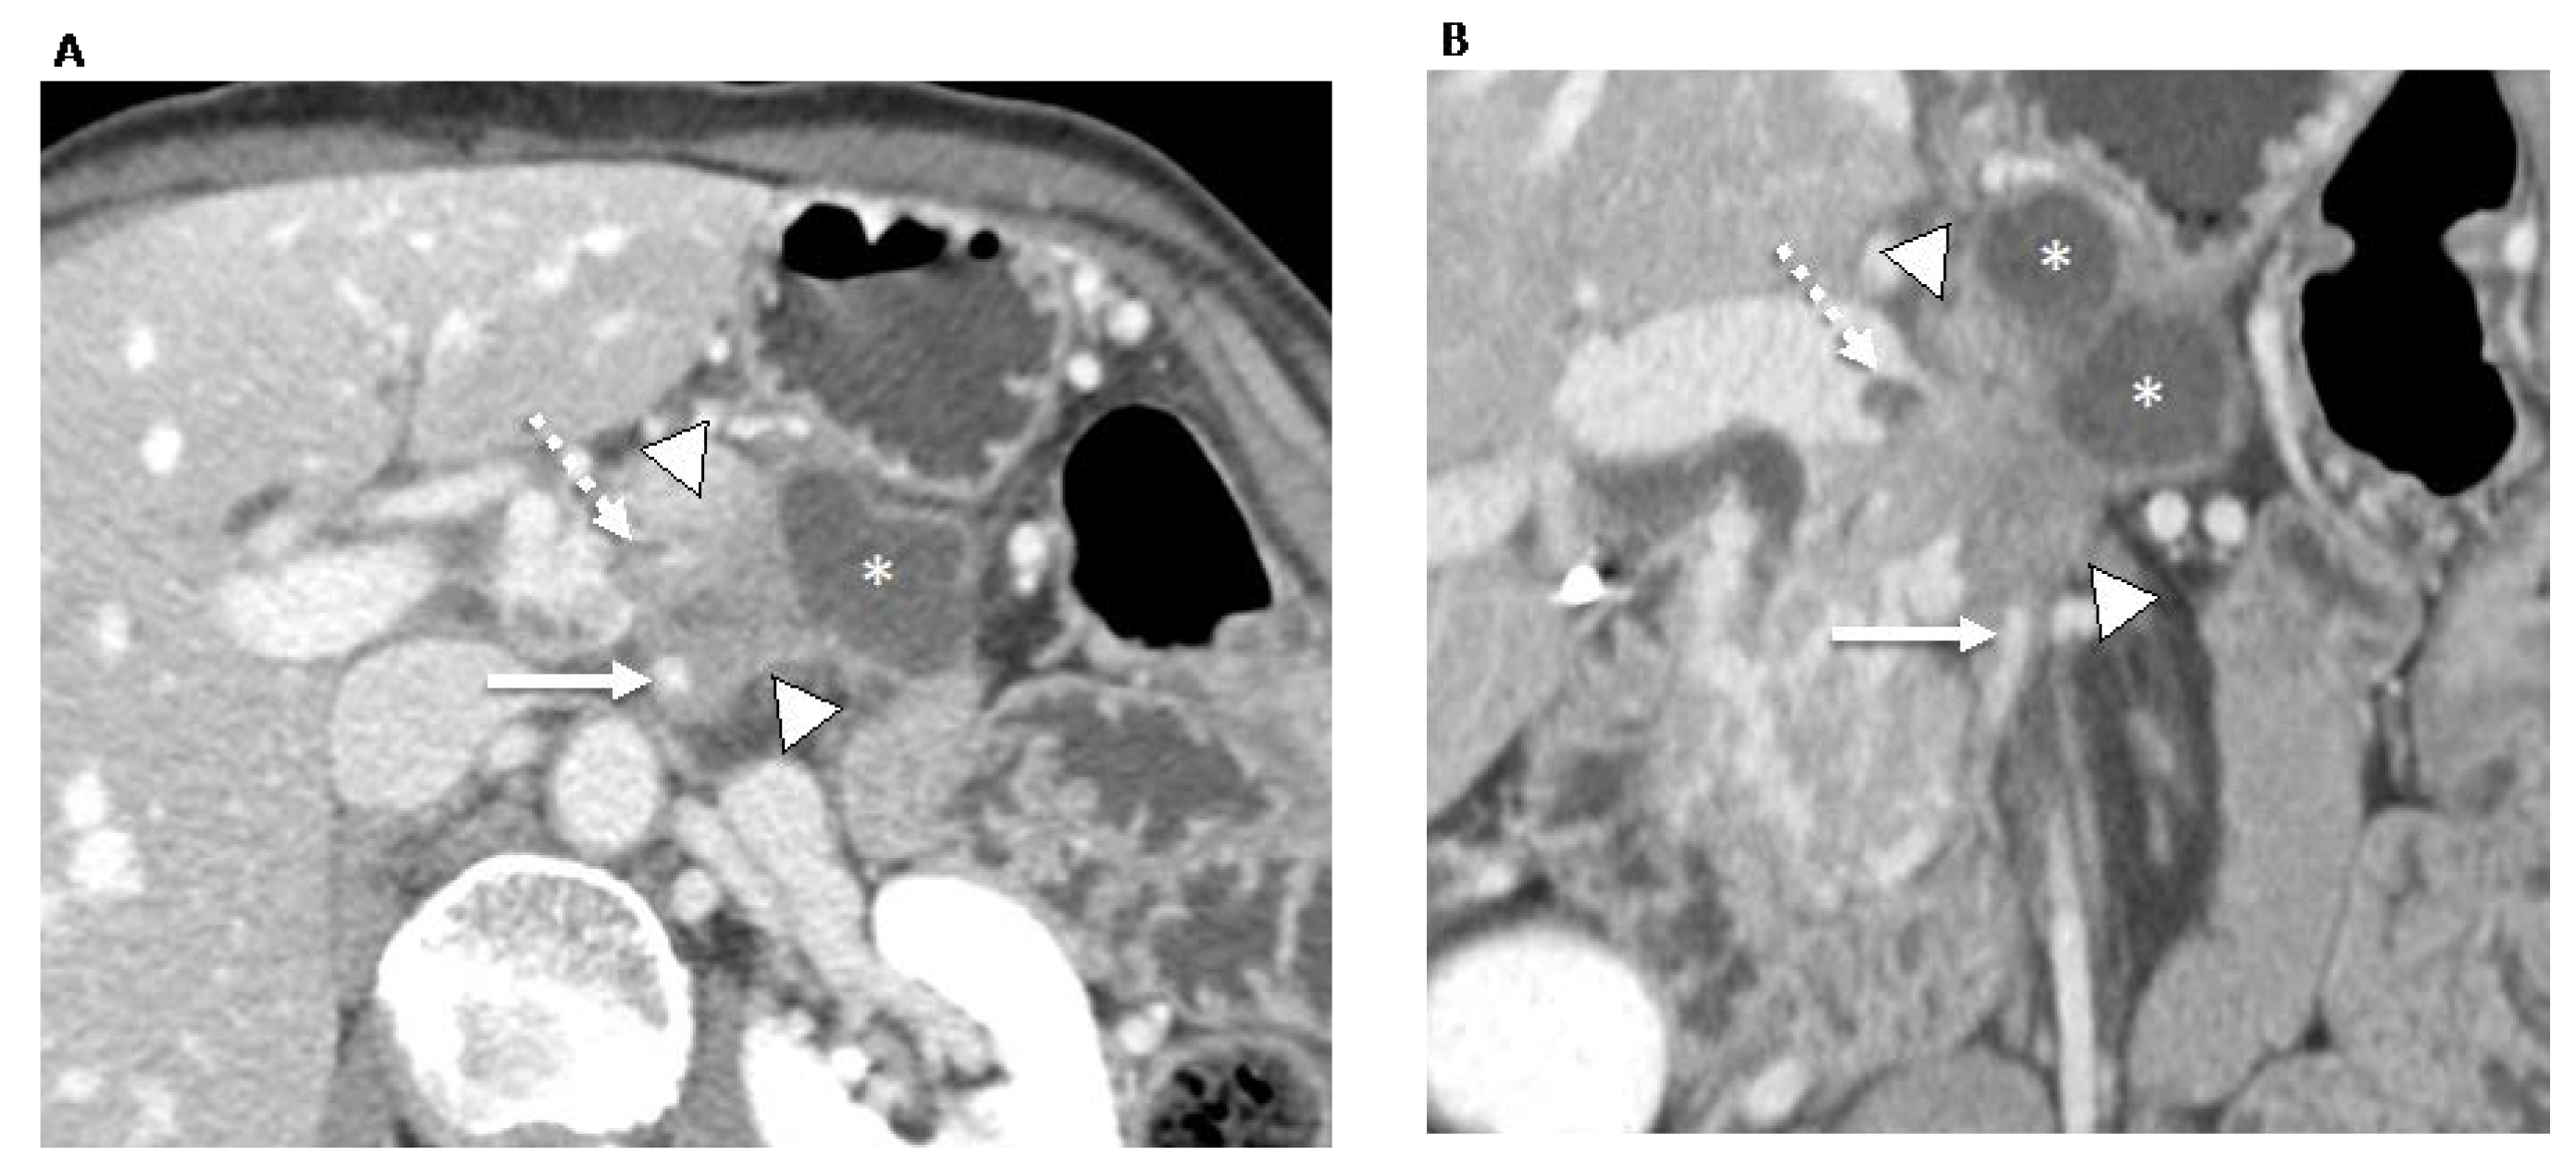

Figure 3.

70-year-old man with locally advanced pancreatic ductal adenocarcinoma. Contrast-enhanced CT in the axial (A) and coronal (B) planes in the portal venous phase shows an ill-defined pancreatic neck and body tumor (arrowheads) with an adjacent pseudocyst (asterisks). The tumor involves the locoregional vessels including encasement (>180°) of the superior mesenteric artery (white arrow) and superior mesenteric vein/portomesenteric junction, which was severely narrowed with small non-occlusive thrombus (dashed arrow). The patient underwent palliative radiotherapy.